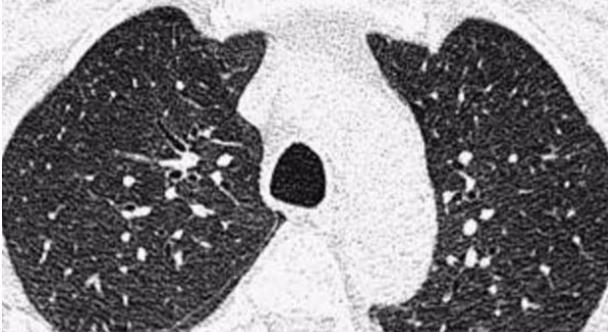

所以说呢,你的肺结节会不会变小消失,主要看你是哪一种结节。当然呢,作为大夫,还是要提醒你:“其实这么小的肺结节,不管是良性的还是恶性的,对你的影响都不会很大,而最重要的是要做到规律的随访。”我们真正担心的是早期肺癌的这一部分患者,因为忽略了结节的存在而造成病情的耽误,当你在规律随访的过程中发现结节变大变实,或者有迅速的变化,及时地手术干预防止病情的进一步恶化,这才是最重要的。

所以说当你查出肺结节后,不用特别的担心,因为(肺结节)大部分都是良性的,根据你结节的大小,按照医生的要求做好随访这才是最重要的。你明白了吗?关注我关注更多的健康知识。